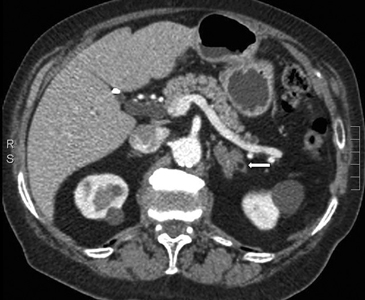

Otros hallazgos que son sospechosos de malignidad, además de los criterios morfológicos ya descritos, son metástasis concomitantes en otro sitio anatómico, heterogeneidad de su estructura, y lavado pobre del contraste en fase tardía. A menudo tienen un lavado lento, menor a un 75% luego de los 15 minutos. No es infrecuente la presencia de necrosis central y hemorragia. En TC se pueden observar como una masa de partes blandas ovoidea o redondeada, o menos frecuentemente como un aumento de tamaño difuso de la glándula suprarrenal. En fase no contrastada la mayoría de las metástasis tienen valores de atenuación mayores a 10 UH, pero existen excepciones como es el caso de las metástasis de melanoma en que los valores de atenuación pueden ser menores, cercanos a los de un adenoma típico. Utilizando estos criterios, la sensibilidad y especificidad para diferenciar mediante TC una metástasis de un adenoma es de 98 y 97%, respectivamente13.

En RM típicamente son hipointensas en secuencias ponderadas en T1 e hiperintensos en T2. La mayoría de las metástasis no muestran caída de señal en secuencias fuera de fase (Figura 20 a y b), porque no contiene lípidos intracelulares. Infrecuentemente las metástasis pueden contener lípido intracelular, como es el caso raro de metástasis de tumores de células renales.